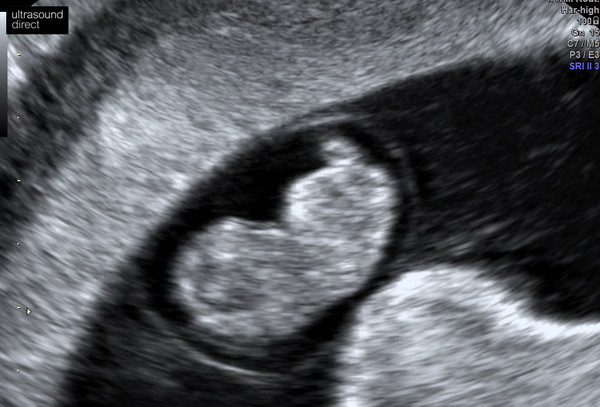

Had my early scan today! All ok with my little bean! Although I was a bit worried when she asked if she could do a trans-vaginal scan....I thought it was because she couldn't see the heartbeat, but she said it was just that my uterus was a bit tilted. Glad she did it though as we got some lovely clear images. Dated at 8+6 which is pretty much bang on my dates!

Loving all these scan pics! Wishing I'd held out for mine for a week or two longer, these slightly later ones look like little babies already!